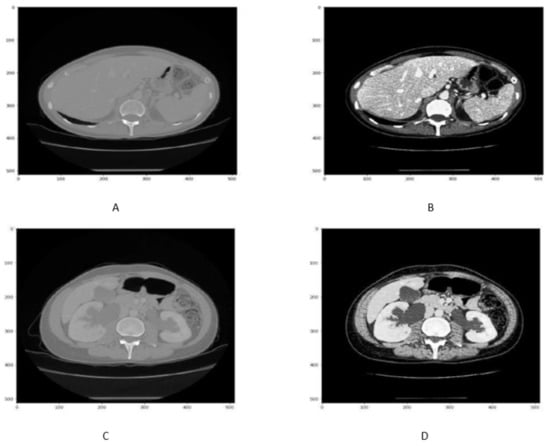

In order to enhance the visualization of the liver, HU windowing is performed at each slice where the HU range of −100 to 400 is selected, as shown in Figure 2. It shows that most organs are occluded in CT image slices without windowing operation, while the image and organs became clearer after HU windowing. Therefore, this HU windowing is performed over all slices before passing them to the next process.

Figure 2.

Figure represents the HU windoing results in (A,B), While Figures (C,D) shows the HU windowing results not having Liver.

Although HU windowing provides good visualization of organs, it was still difficult to differentiate between the liver and adjacent tissues. Therefore, histogram equalization was applied to the image obtained after window processing and then normalized in the range of [0, 1] as shown in Figure 3. It can be seen that as compared with Figure 2A,B, the organs boundaries are more evident in Figure 3C,D after histogram equalization.

Figure 3.

Figure shows that the CT slice (A,B) before histogram equalization, While CT slice (C,D) after histogram equalization.